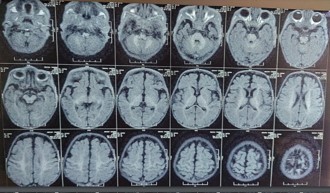

Figure 2: MR TIWI image shows appropriate myelination for the age with mild cerebral atrophy.

HRCT revealed consolidations in bilateral upper and lower lung lobes with mild hepatosplenomegaly and borderline cardiomegaly MRI Brain revealed: cerebral atrophy, thinning of corpus callosum and symmetric DWI restriction in globus pallidi, PLIC, peritrigonal white matter, optic radiations, brainstem and medial temporal gyri (which raised the suspicion of INBORN ERROR OF METABOLISM).